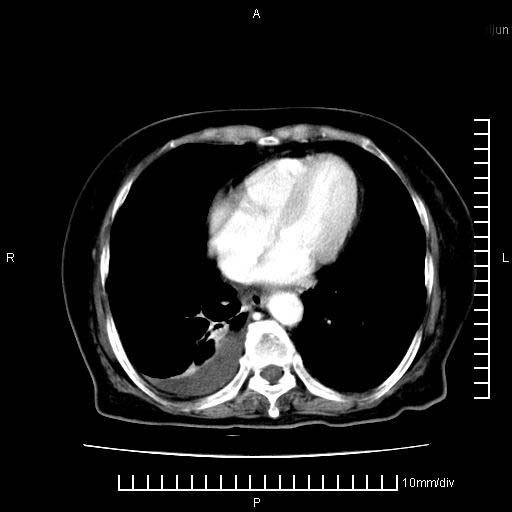

上腹疼痛月余,外院核磁诊断胰腺癌。现临床示右下腹可明显触及包块,可片子上怎么没有看到?

1.胰腺颈体部癌。

2。腹腔积液。

3。右胸腔积液,伴右肺下叶部分萎陷。

4。右肾盂囊肿。

1。胰腺ca伴腹膜腔转移

2。肝左叶低密度灶,考虑转移可能

胰腺结构模糊,胰尾部见囊性包块,周围脂肪密度增高,左肾前筋膜增厚,胸水、腹水。不符合胰腺ca伴腹膜腔转移。考虑胰腺炎伴假性囊肿形成、胸腹腔积液。

1、考虑胰腺癌伴腹膜腔转移,胸腹水。

2、肝脏转移可能。

3、右肾盂囊肿。

1)考虑胰腺癌并胰腺假性囊肿形成。2)肝内低密度灶,不排除转移。3)右肾盂积水。4)腹水。5)右侧胸腔积液并右肺下叶部分膨胀不全。

考虑胰腺ca伴腹膜腔转移、肝左叶转移、右肾积水。右胸腔积液。